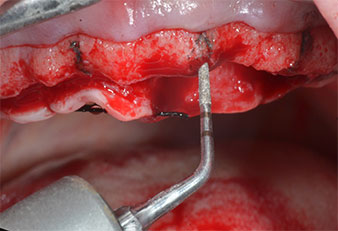

Wegen des relativ harten Knochens (D2) an den Positionen 11 und 21 wurden die 10 mm langen Implantatlager in diesem Bereich abschließend mit einem 4-mm-Spiralbohrer, dem chirurgischen Winkelstück WS-75 L von W&H und dem W&H Implantmed Implantologiemotor in Verbindung mit dem optionalen W&H Osstell ISQ module präpariert. Im Gegensatz dazu wurde der weiche Knochen der Implantatlager im Seitenzahnbereich mit dem Piezomed I3P auf den abschließenden Durchmesser von 3 mm erweitert. Die Implantate wurden dann transgingival eingesetzt, die Einheildauer betrug drei Monate (Abb. 6-10). Die vorhandene Prothese wurde auf vier provisorischen Implantaten abgestützt (Abb. 8).